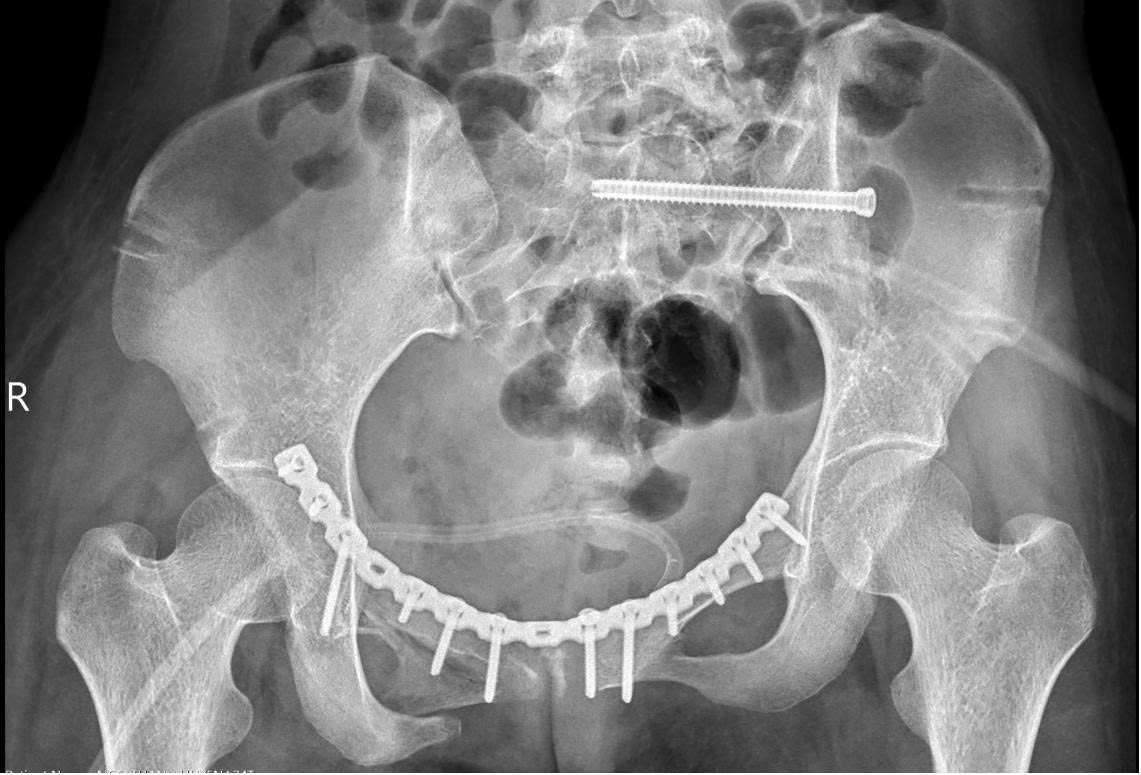

“Vì vậy, mục tiêu điều trị là phục hồi cấu trúc giải phẫu khung chậu và cố định vững chắc bằng nẹp vít, giúp bệnh nhân sớm vận động trở lại. Ở trường hợp này, khung chậu mất vững cả cung trước và sau, nên sau khi nắn chỉnh, chúng tôi cố định cung trước bằng nẹp vít và cung sau bằng vít xốp”, BS Khanh chia sẻ.

Hình ảnh xương chậu trên phim chụp sau nắn chỉnh - Ảnh BVCC